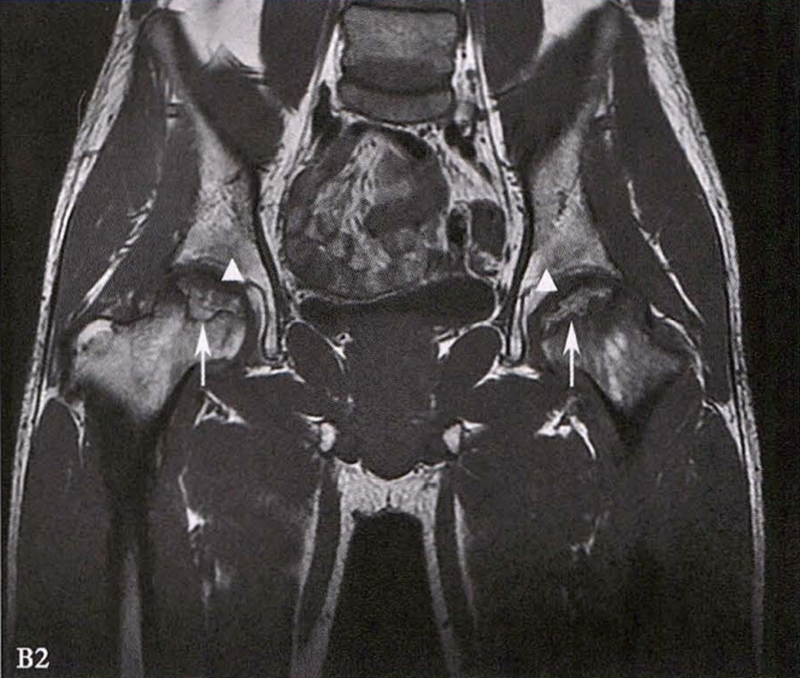

B.男性,31岁,双侧股骨头坏死,双侧均为Ⅲ期。X线片示双侧股骨头密度不均、股骨头稍变扁(B1)。MRI(T1加权像)示股骨头内多发不规则信号带(B2),股骨头内凸向大转子的双线征(白色箭)和软骨下骨骨折(白色三角)。